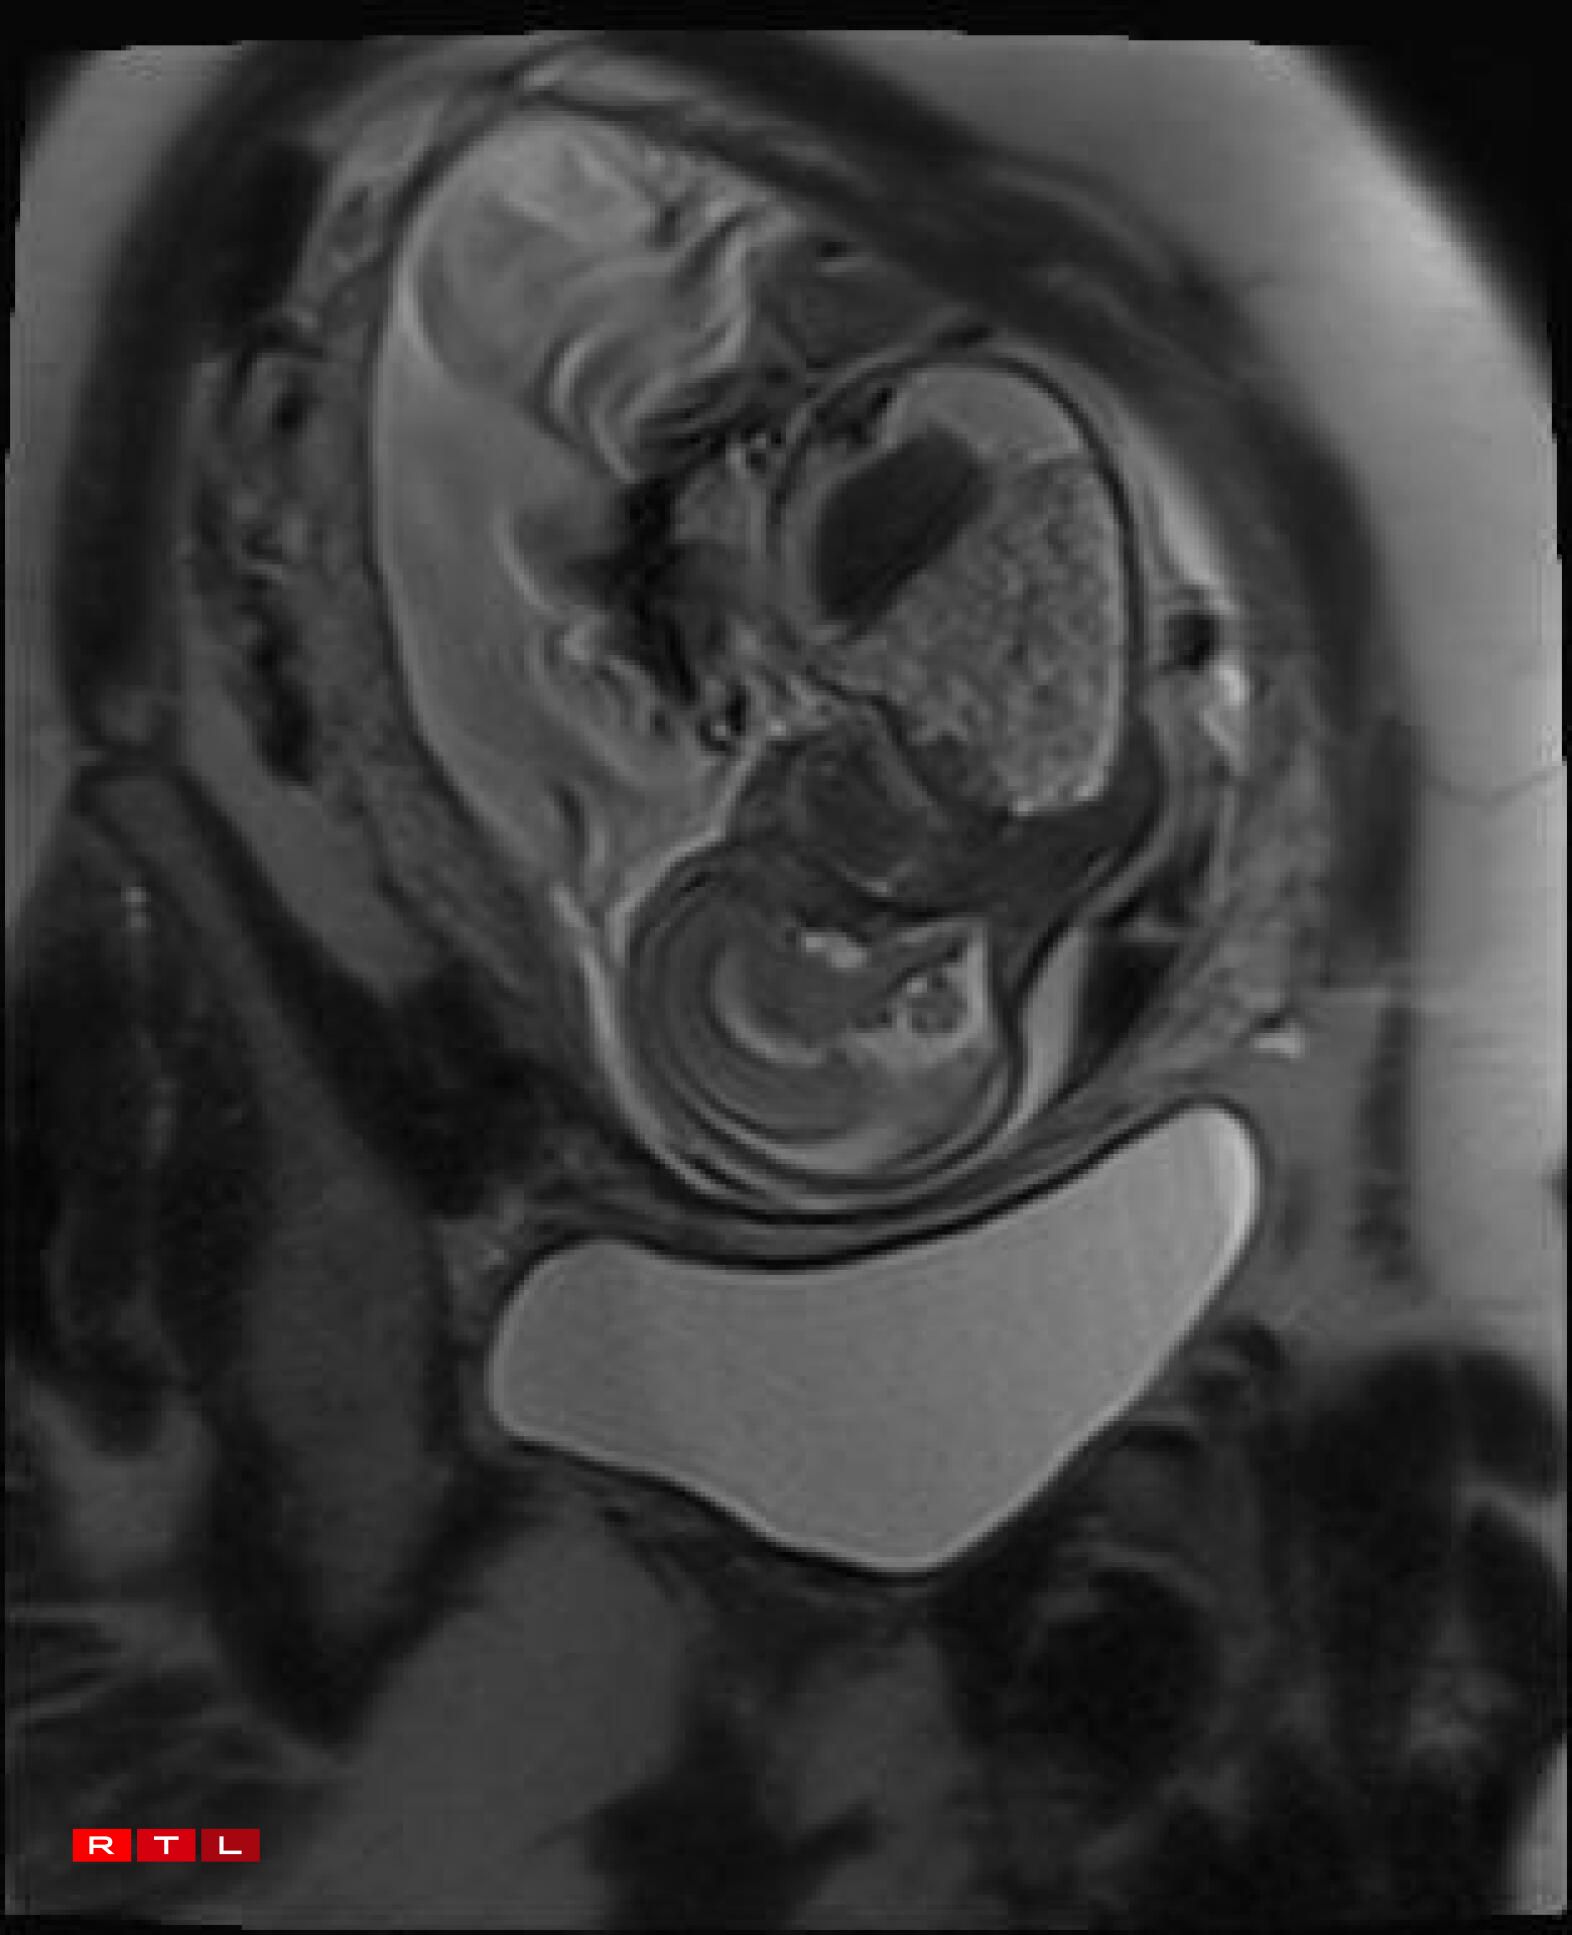

Lis was therefore referred to the Centre Hospitalier de Luxembourg (CHL), where further examinations led to a diagnosis. Noa was found to have a congenital pulmonary airway malformation (CPAM). Doctors explained that a large mass of cysts had formed in his chest, compressing his heart and disrupting his circulation. This, in turn, caused the fluid retention observed during the initial scan.

In Noa’s case, the CPAM was caused by a malformed aorta: a blood vessel had branched toward the lungs and was feeding the cysts. The condition is known as a sequestration. Professor Kohl proposed the following intervention:

“He would go through my abdomen with two small incisions to reach the amniotic sac, then pass through Noa’s chest to the heart, where he would cauterise the blood vessel that was feeding the cysts using a small electric current. From there, we could hope that the cysts would shrink and the lung could begin to develop”.